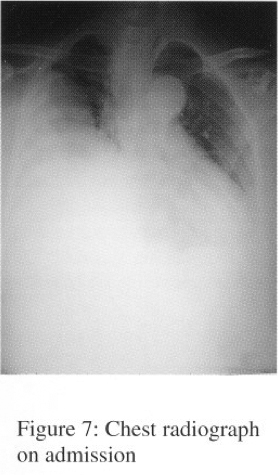

In Sept 2003, she was admitted to NDH for progressive dyspnoea and cough. CXR showed huge right lung opacity with right sided pleural effusion (Serial CXRs shown on figures 1-3).

Arterial blood gases showed type I respiratory failure (pH7.44,PaC02 5.52,Pa02 7.30, HC03 27.2, Sa02 89%). Bronchoscopy showed a bulge seen over posterior segment of right upper lobe bronchus. Bronchial aspirate showed atypical cells. Transbronchial needle aspiration (TBNA) over right upper lobe bronchus was negative for malignancy. CT scan of thorax showed huge right lobulated lung mass with heterogeneous intra-lesional contrast enhancement and significant mass effect with displacement of the mediastinum towards left side and collapsed right upper, middle and lower lobes. Right sided pleural effusion was also present (Figure 4). The radiological feature was suggestive of mesothelioma, with differential diagnosis included other sarcoma.